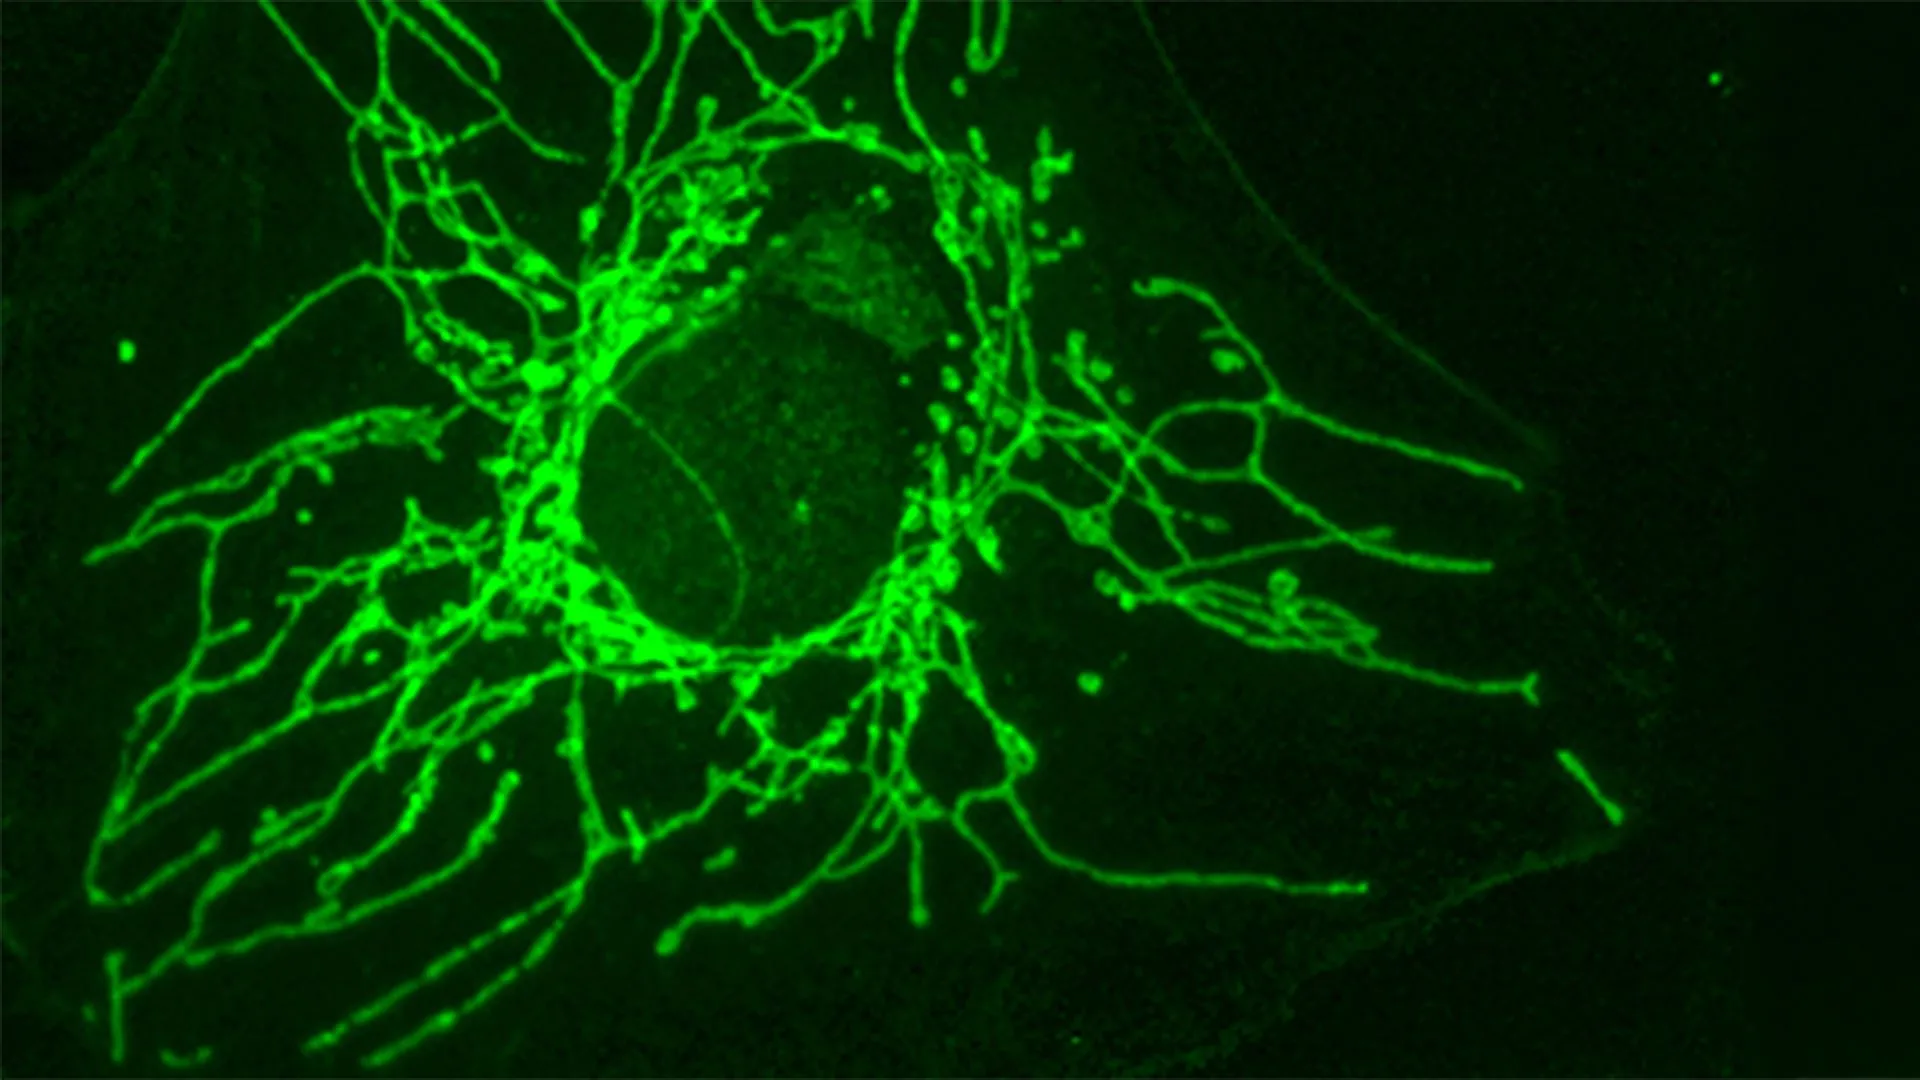

Further detailed mechanistic investigations, conducted in close collaboration with Professor Roland Lill and his esteemed research group at the University of Marburg, delved into the precise molecular pathways through which D-Cys exerts its cytotoxic effects on cancer cells. The collaborative effort elucidated that D-Cys functions by inhibiting a crucial enzyme, known as NFS1, which is located within the mitochondria – the vital organelles responsible for cellular energy production. NFS1 plays an indispensable role in the biosynthesis of iron-sulfur clusters, complex molecular structures that are fundamental cofactors for a wide array of cellular processes. These processes include, but are not limited to, cellular respiration, the synthesis and repair of DNA and RNA, and the maintenance of genomic stability.

The consequence of NFS1 inhibition by D-Cys is a cascading disruption of essential cellular functions. Cancer cells, reliant on their heightened metabolic activity for rapid proliferation, experience a significant decline in their respiratory capacity. Concurrently, this disruption leads to an accumulation of DNA damage, and ultimately triggers an arrest of the cell cycle, effectively halting the uncontrolled division that characterizes malignant growth. This multi-pronged assault on fundamental cellular machinery effectively incapacitates the cancer cells, preventing their continued expansion.